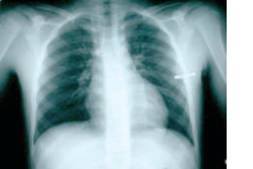

Radiology of the chest

The X-Ray is a portable supine AP.

1. Check adequacy

Inspiration: 6 anterior rib visible on the X-Ray above the diaphragm:

- Penetration: able to see vertebral disc though heart Normal chest x-ray

2. Alignment

- Medial ends of clavicles symmetrical on either side of, and equidistant from, the vertebral column;

- Anterior ends of ribs symmetrical on either side of, and equidistant from, the vertebral column.

3. Apparatus

Check position of all internal tubes - Endotracheal tube, Nasogastric tube, etc.

4. Bones

Check all bones present on the X-Ray i.e. spine, ribs, scapula, clavicle and, proximal humerus.

5. Joints

Check acromioclavicular joint and the shoulder joint.

6. Borders /Mediastinum

- Check that apices are clear

- Check that costophrenic angles are clear

- Check that costocardiac angle are clear.

7. Diaphragm

Check it is clearly defined and normally situated.

8. Lungs

Check: -The trachea is central; -The lungs are fully inflated; check for lung markings throughout;

- The lung fields are symmetrical;

- Horizontal fissure in correct position ;

Remember the X-Ray is taken supine

so pneumothorax and haemothorax will differ from an erect

film

9. Heart

Check: -The size is normal. This is difficult to interpret in an AP film but it is generally 2/3 of the lateral diameter.

- Position - is there any deviation?

Examples of chest x-rays

Right lower lung contusions Left-sided pneumothorax: